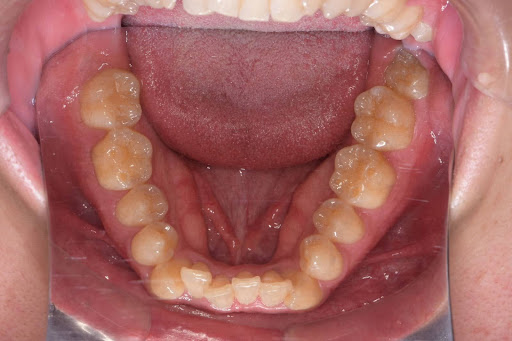

【症例写真】豊富な経験に基づき、歯の重なりやアーチの形状を美しく改善します。

Before

After